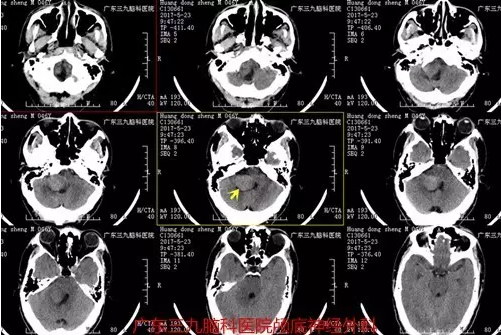

图1:术前CT提示类圆形稍高密度占位性病变

非典型脉络丛乳突状瘤在颅脑MRI上呈T1等或稍低信号,T2高或等信号,多为囊实性改变,不同程度强化,CT呈稍高密度,瘤内多见钙化影,应与脑膜瘤及听神经瘤相鉴别,本例MR为囊实性改变,其实性部分较大,增强后呈欠均匀明显异常强化,囊性部分位于周缘,边界部分欠清,大小约为95px×87.5px×112.5px,CT呈稍高密度影为主。基本符合病变特征。